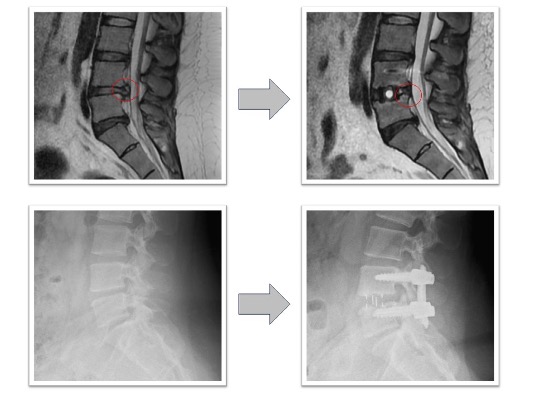

腰椎固定術実例(OLIF症例、*患者様の許可を得て掲載しています)

椎間板ヘルニア(図1)

体動困難を伴う激烈な下肢痛に対してL4/5の固定術を実施。術前に認められていたL4/5の椎間板ヘルニアがOLIFによる固定術後、間接除圧効果などによって消失しています(図1、赤丸)。レントゲンでは椎間ケージと腰椎L4とL5を固定する椎弓根スクリューが確認できます(図1、下段)。本症例の傷は左わき腹に4-5cmと、背部のスクリュー刺入部位に2㎝弱の傷が4つとなります。術後、痛みは消失しました。

図1